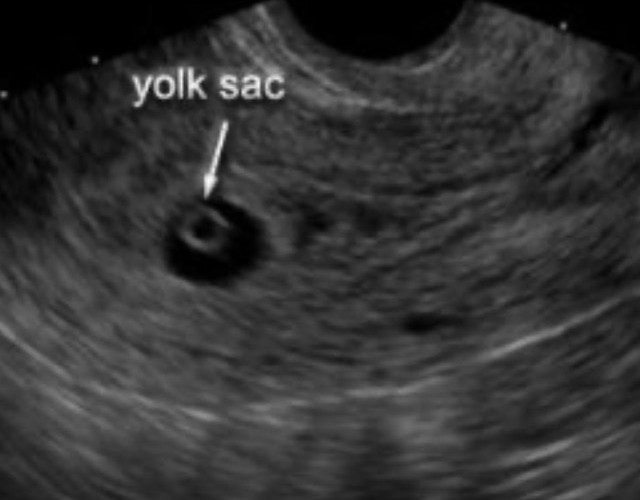

“Did the doctor tell you they had seen a yolk sac?” the technician said.

Gulp. “Yes.” I answered. She kept looking. A few mins later…

“Okay, I see it, barely a yolk, but I am so sorry, I can’t see an embryo.”